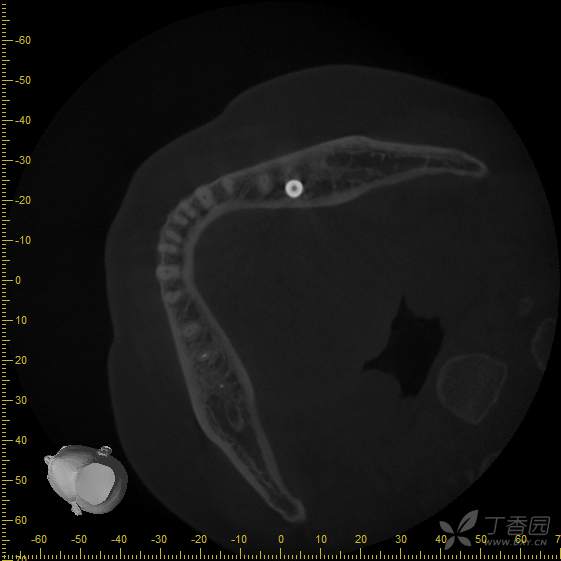

接诊时,36种植牙松1-2°,颊侧牙龈未见明显红肿。拍摄cbct后可见种植体周骨结合丧失,大量低密度影,骨吸收至根尖1/3,种植体浮出。

取出后的种植体,种植体周围不见任何骨结合。

种植体取出后,袖口可见大量肉芽组织。

取出种植体,刮净肉芽组织,碘酊灼烧,生理盐水,洗必泰大量冲洗,缝合,嘱3个月后复查。